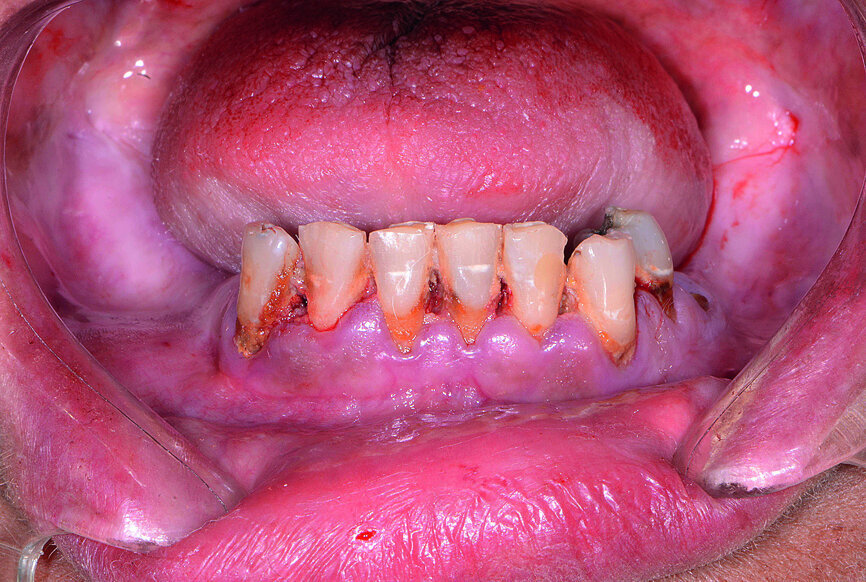

Fig. 13: Mandibular arch anaesthetised.

Next, the patient’s untreatable mandibular teeth (Fig. 13) were extracted using the Physics Forceps (GoldenDent), a flap was reflected, and an alveoloplasty was performed. A bone-supported guide was seated in order to control the location and angulation of the implant osteotomies (Fig. 14). As the Hahn Tapered Implants were threaded into place, their deep, sharp threads engaged the walls of the socket sites and helped maintain proper position toward the lingual aspect. Because of anticipated tissue swelling as a result of the bone levelling procedure, 5 mm high healing abutments were connected to the implants in the lower arch (Fig. 15). The immediate dentures were soft-relined with Mucopren (Kettenbach) to seat over the Hahn Tapered Implant Healing Abutments, the hourglass shape and undercuts of which provided a degree of retention that enhanced dental function for the patient during healing (Fig. 16).